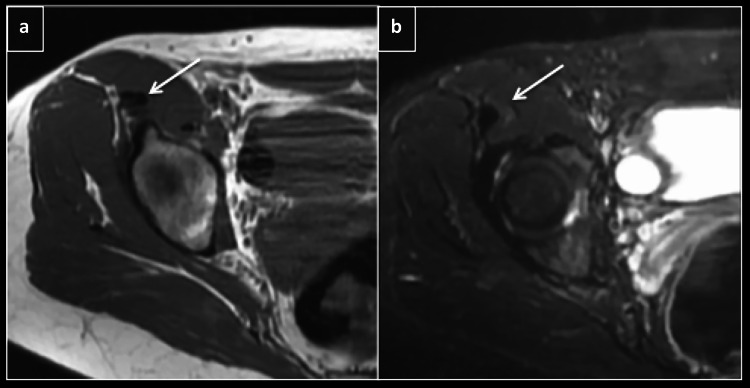

Fig. 1.

Axial T1 (a) and STIR (b) showing direct head of rectus femoris (arrow) with subtle edema